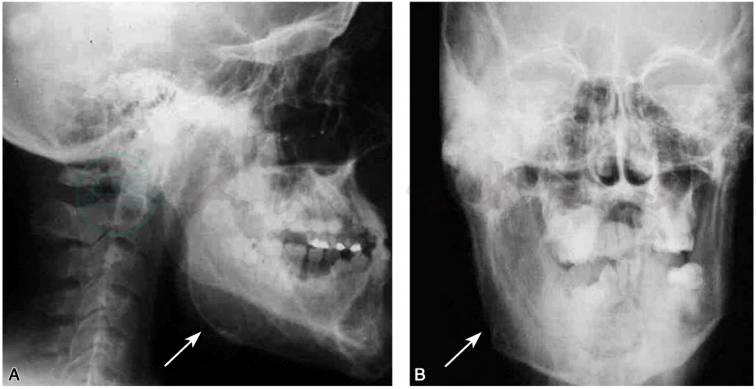

1.X线片可显示病变侧骨质或牙齿增粗(Islam et al,2007)(图1)。 脑 CT和MRI检查显示病侧皮下结缔组织、骨骼及其他脏器均呈肥大改变(Bou-Haidar et al,2010)(图2)。

图1面偏侧肥大症患者颅骨X线片

A.头颅和下颌骨侧位像,显示右髁、冠状突和下颌体明显的骨性增大;B.前后位像,箭头显示下颌骨畸形区